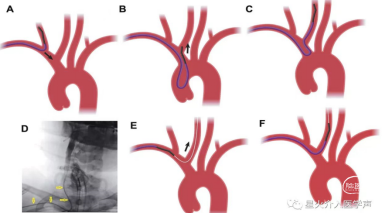

1、全麻下桡动脉入路:利用超滑导丝交换技术直接送入5F中间导管(下图1)。

2、中间导管到位造影基底动脉闭塞,向左侧椎动脉返流(下图3)。

3、微导管造影:微导管位于真腔,右侧大脑后动脉P3段(箭头所指)闭塞(下图2、4)。

4、支架释放:4*20取栓支架送入后可见血流通畅,左侧大脑后动脉仍闭塞。取栓后基底动脉通畅大脑后动脉P3段闭塞(下图5)。

决定取栓,微导丝通过,少量血流通过,血栓(箭头所指)更加明显了,回撤支架后造影:血流通畅,血管痉挛解除。

对于本次病例直接中间导管建立通路,中间导管到位造影基底动脉闭塞,4*20mm支架基底动脉取栓,小支架3*15mm大脑后动脉钳夹取栓。3*15mm小支架对血管刺激性更小,取栓术后血流通畅,未出现与支架相关并发症,且一把拉通,是远端血管取栓的一个选择。